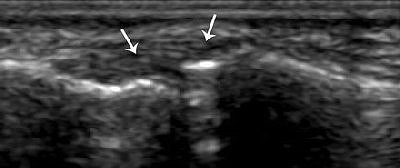

![]()  |

| UCL strain in a 32-year-old man. Coronal US scan of the thumb shows diffuse thickening of the UCL (arrows) without a tear. MCP = metacarpal, PP = proximal phalanx. |

"The spectrum of UCL injury includes strain, partial-thickness tear, and full-thickness tear. We outline a simple method of performing (ultrasound) of the thumb and discuss the spectrum of common acute disorders encountered with particular emphasis on UCL injuries," they wrote.

In their sample of 32 patients, ultrasonography was performed with the hand placed flat on a table. A 12- to 23-MHz linear probe was slid from the second finger onto the first metacarpophalangeal joint to obtain either a transverse image of the UCL or a longitudinal one.

In general, the UCL tear is considered displaced when it is retracted or folded on itself. It will also move proximal to the adductor aponeurosis, which creates the appearing of a yo-yo on a string, according to the authors. The yo-yo portion is the torn, displaced UCL.